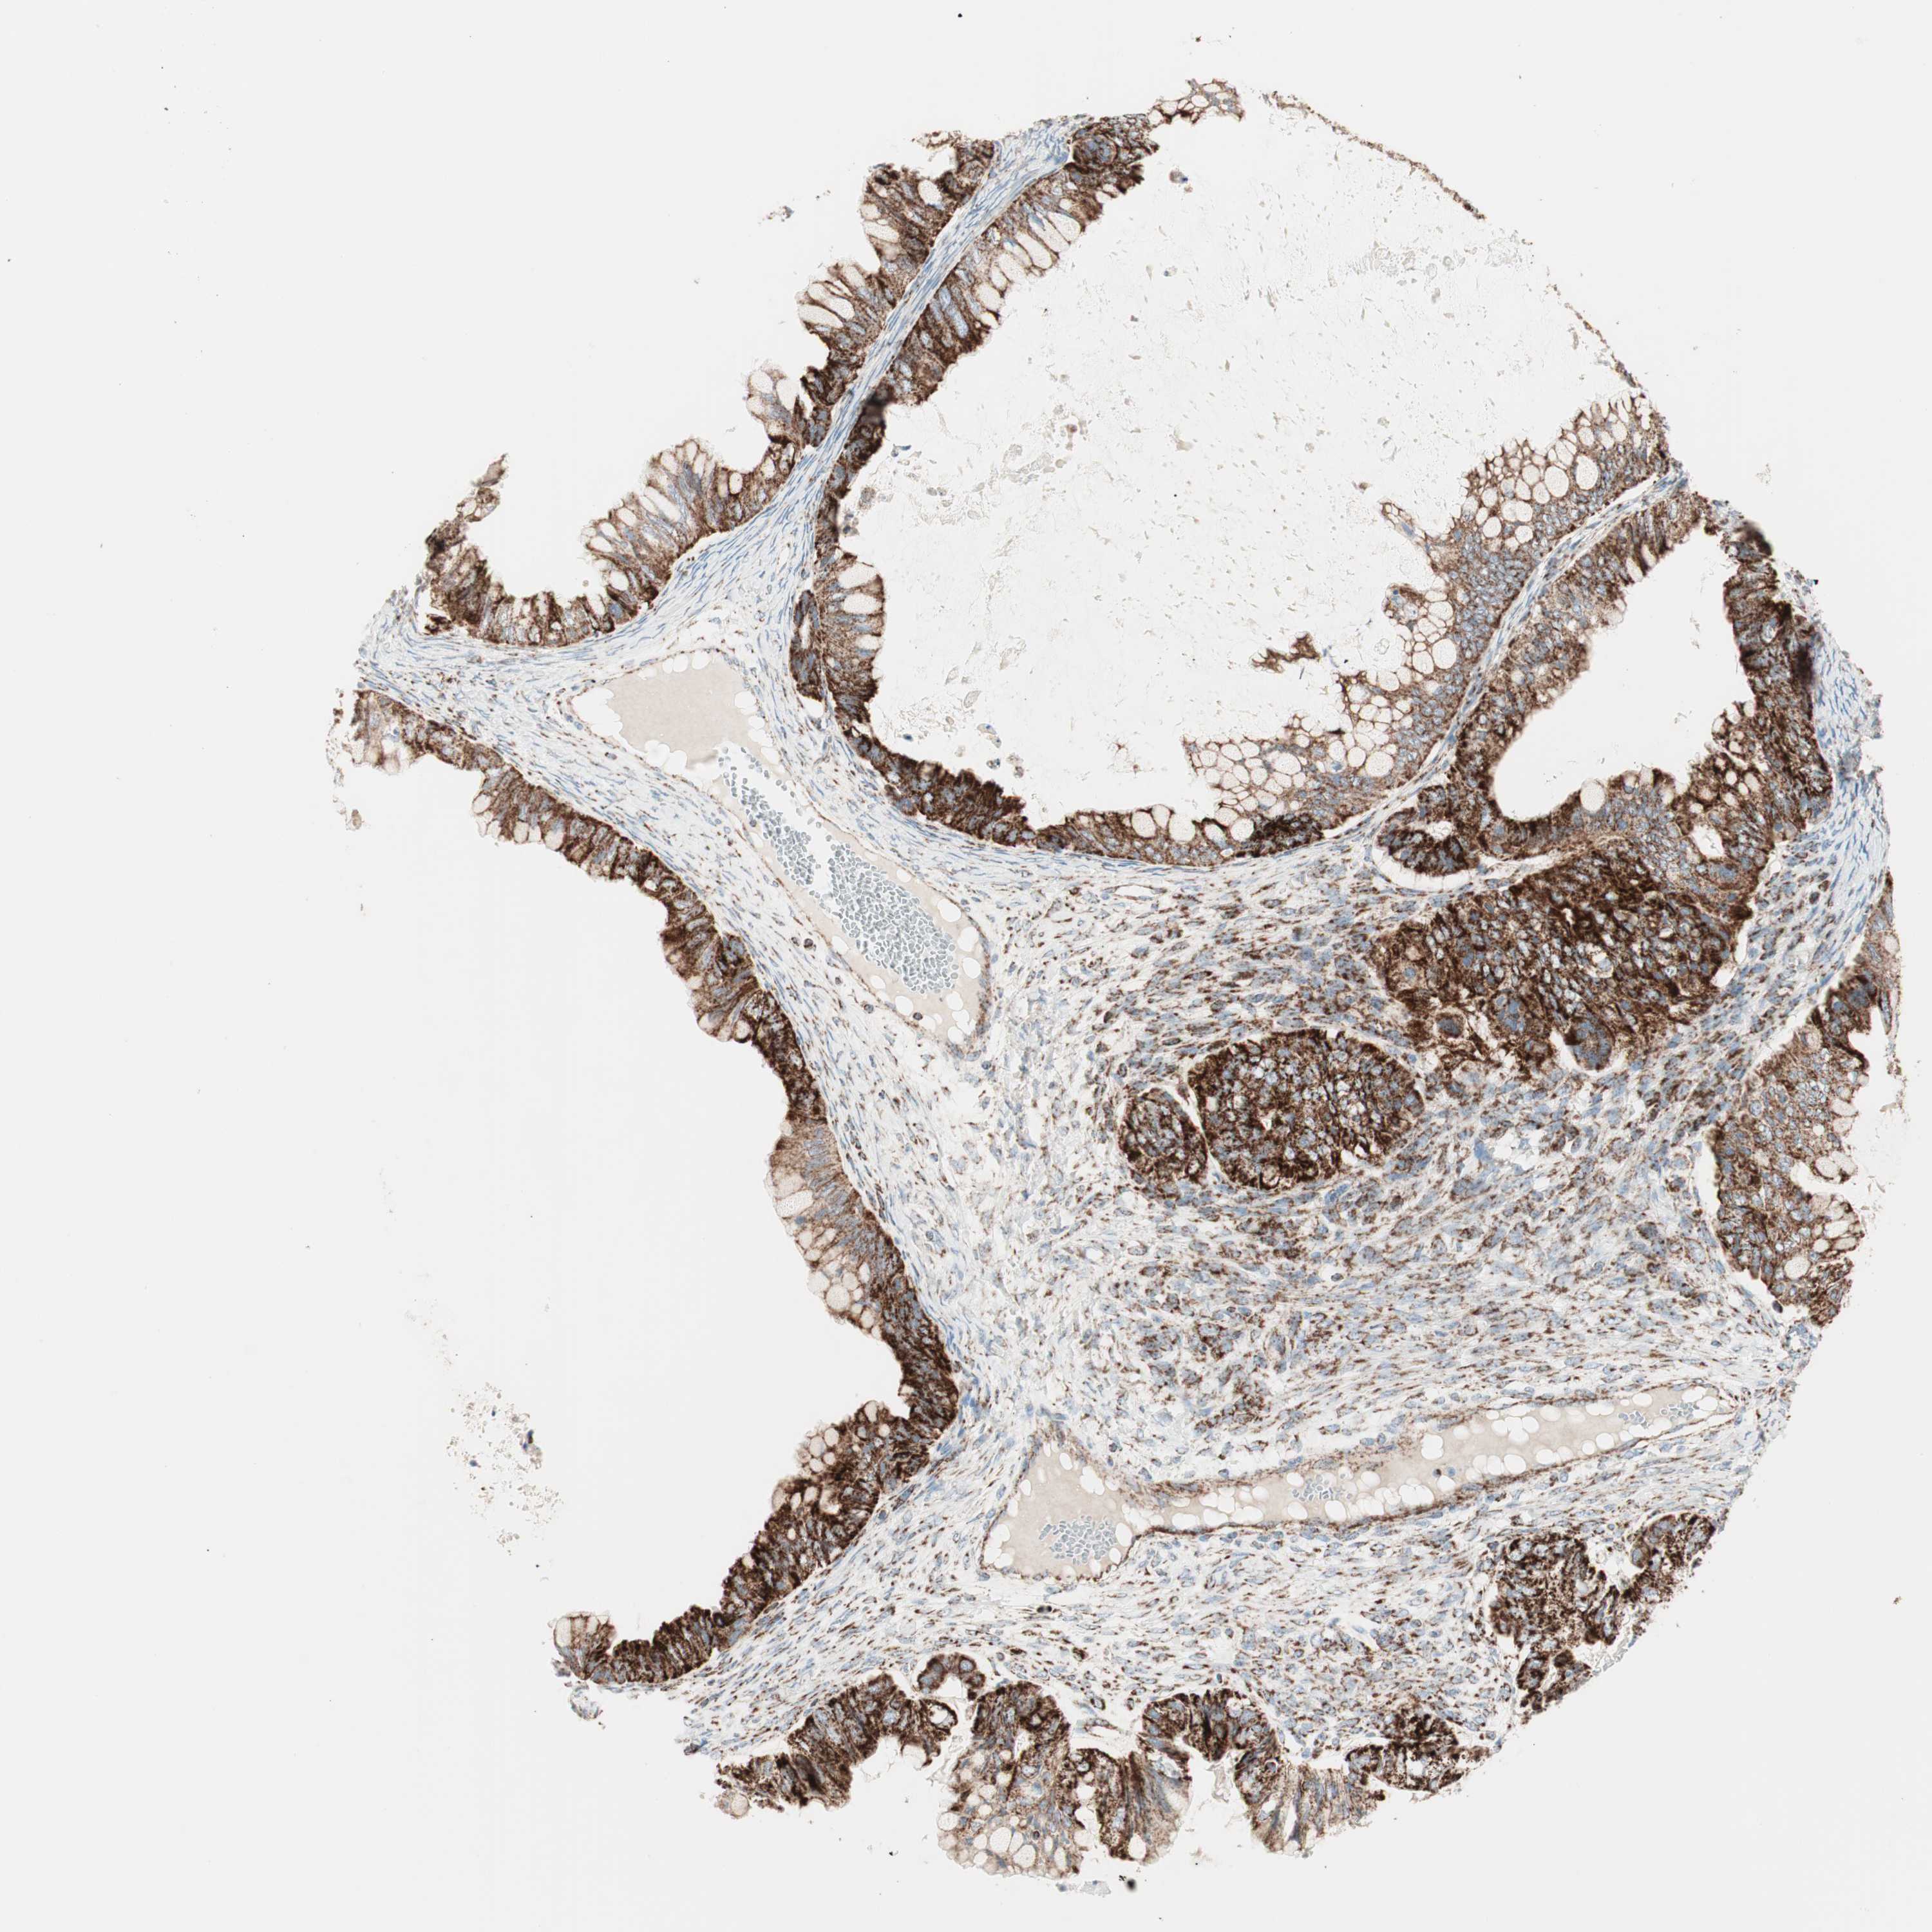

OVARIAN CANCER - Protein expressioni

A mouse-over function shows sample information and annotation data. Click on an image to view it in a full screen mode. Samples can be filtered based on level of antibody staining by selecting one or several of the following categories: high, medium, low and not detected. The assay and annotation is described here.

Note that samples used for immunohistochemistry by the Human Protein Atlas do not correspond to samples in the TCGA dataset.

Antibody stainingi

Antibody staining in the annotated cell types in the current human tissue is reported as not detected, low, medium, or high, based on conventional immunohistochemistry profiling in selected tissues. This score is based on the combination of the staining intensity and fraction of stained cells.

Each image is clickable and will lead to virtual microscopy that enables deeper exploration of all samples and also displays staining intensity scores, fraction scores and subcellular localization as well as patient and tissue information for each sample.

Antibody HPA011562

Antibody CAB005585

Cystadenocarcinoma, serous, NOS

Carcinoma, endometroid

Cystadenocarcinoma, mucinous, NOS

Carcinoma, NOS